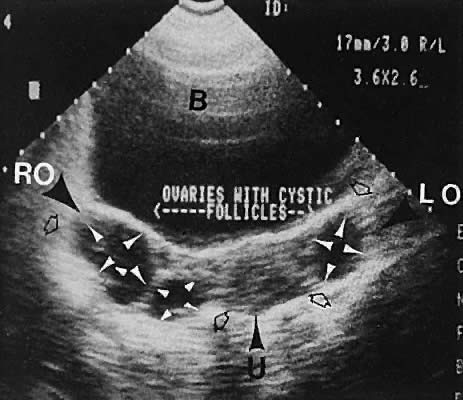

Με τον όρο πολυκυστικές ωοθήκες περιγράφουμε εκείνες τις ωοθήκες που περιέχουν πολλές μικρές κύστεις, οι οποίες συνήθως δεν ξεπερνούν τα 8 χιλιοστά σε μέγεθος, και που εντοπίζονται τις πιο πολλές φορές ακριβώς κάτω από την επιφάνεια της ωοθήκης. Οι μικρές αυτές κύστεις είναι ωοθυλάκια που περιέχουν ωάρια, λόγω όμως ορμονικών διαταραχών, τα ωοθυλάκια αυτά δεν έχουν αναπτυχθεί πλήρως και παρουσιάζουν στασιμότητα στη πορεία εξέλιξης τους. Οι πολυκυστικές ωοθήκες είναι συχνές στις γυναίκες και απαντώνται περίπου στο 20 – 30% των γυναικών.

Η διάγνωση γίνεται με βάση τα κλινικά συμπτώματα, τη διενέργεια υπερηχογραφήματος των ωοθηκών και έναν βασικό ορμονικό έλεγχο.